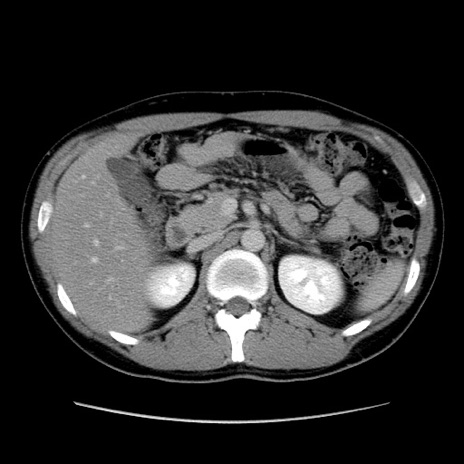

症例36(横断像)

【症例】20歳代 男性

【主訴】心窩部痛

【現病歴】今朝より上腹部痛あり。一旦軽快していたが再度出現したため救急要請。昨日夕に白身の魚を含む刺身を食べた。

【身体所見】BP 136/89mmHg、HR 74/min、BT 37.0℃、腹部:膨満、軟、心窩部に圧痛あり。反跳痛なし、筋性防御なし、腸雑音やや亢進あり。

【データ】WBC 17700、CRP 0.48